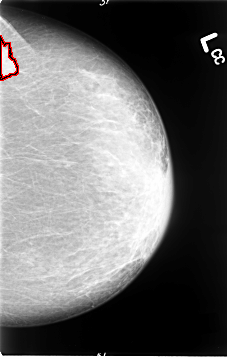

B_3064_1.LEFT_MLO

B_3064_1.LEFT_CC

LEFT_MLO LINES 4640 PIXELS_PER_LINE 2912 BITS_PER_PIXEL 12 RESOLUTION 50 OVERLAY

FILE: B_3064_1.LEFT_MLO.OVERLAY

TOTAL_ABNORMALITIES 1

ABNORMALITY 1

LESION_TYPE MASS SHAPE IRREGULAR MARGINS SPICULATED

ASSESSMENT 5

SUBTLETY 5

PATHOLOGY MALIGNANT

TOTAL_OUTLINES 1

BOUNDARY